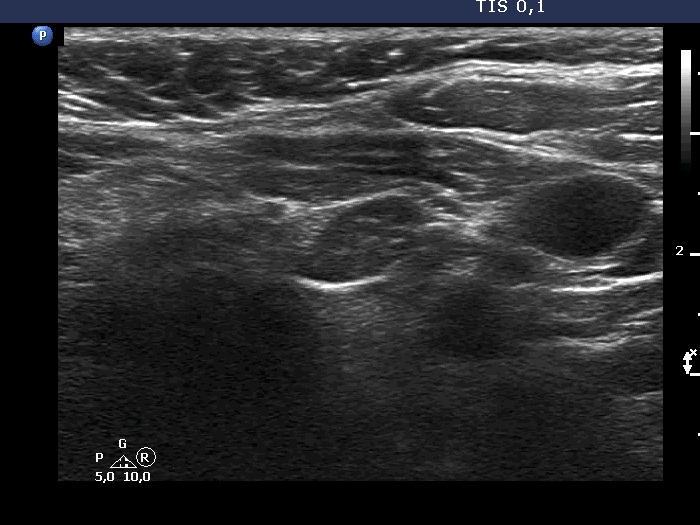

Ultrasonography. The thyroid was echonormal. According to the PET-positive lesion, there was a moderately hypoechoic nodule in the middle-dorsal part of the left lobe. The lesion presented with perinodular blood flow. In the transverse section, it appeared that there was another nodule in the lower pole of the lobe. At the same time, based on the longitudinal section, it was not an oval, nodule-like lesion. The mass proved to be longitudinally elongated in the caudal direction and was avascular.

An anatomical structure running perpendicular to the transducer looks round or oval, and it can look deceptively like a discrete lesion. If this occurs in the thyroid region, it can be mistaken for a nodule. The most common examples of this are the carotid artery, the jugular vein, and the esophagus, the latter usually appears on the dorsal surface of the left lobe of the thyroid gland. The key is always to examine the patient in two perpendicular planes. An examination parallel to the anatomical structure (in this case in the longitudinal section) shows that it is a tube-like, longitudinal structure. In this case, it was very likely a dorsal muscle.